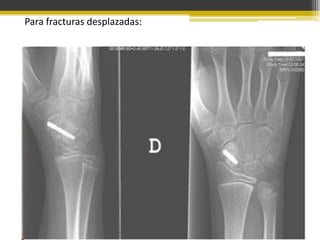

Para fracturas desplazadas:

Tratamiento

• Desplazamiento poco frecuente, si existe,

reducirlo.

• Yeso tipo Böhler.

• Se inmoviliza la muñeca en posicion de

“sostener un vaso”

• Se retira el yeso 6 semanas despues y se

toma otra radiografia.

• Si a las 18 sem no se consolida se da tx qx

con injerto oseo